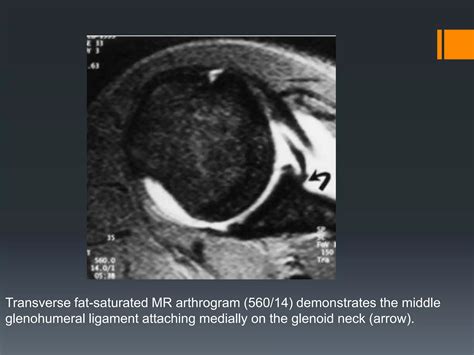

Labral Tear - Shoulder - Conditions - Musculoskeletal - What We Treat ...